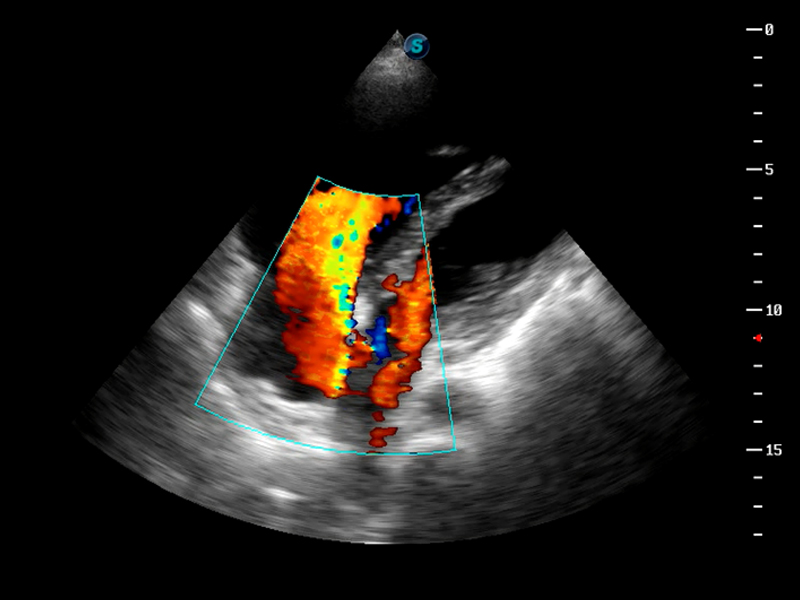

S9便携式彩色多普勒超声诊断仪是玖鼎集团研发的高端便携彩超设备,外观设计新颖、产品性能卓越。S9在便携超声领域采用了突破传统的触摸屏交互设计,并以先进的软件硬件技术和设计理念,为您带来清晰的图像质量、稳定的工作性能和便捷的操作体验。

AutoC智能血流追踪